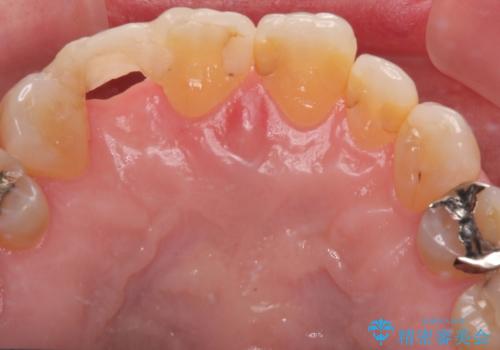

- 前歯のインプラント治療を検討して様々医院を探していたところ、1回の手術で治療ができるとのことで来院された患者様です。

長期間の治療と外科処置の回数が多くなることを懸念して、なかなかインプラント治療に乗り出せなかったそうですが、1DAYインプラントというものがあることを知り、当院にいらっしゃいました。

仮歯を事前に用意し、インプラント埋入時に即日で仮歯を装着する、即時荷重インプラントの計画で治療を進めて行くこととしました。